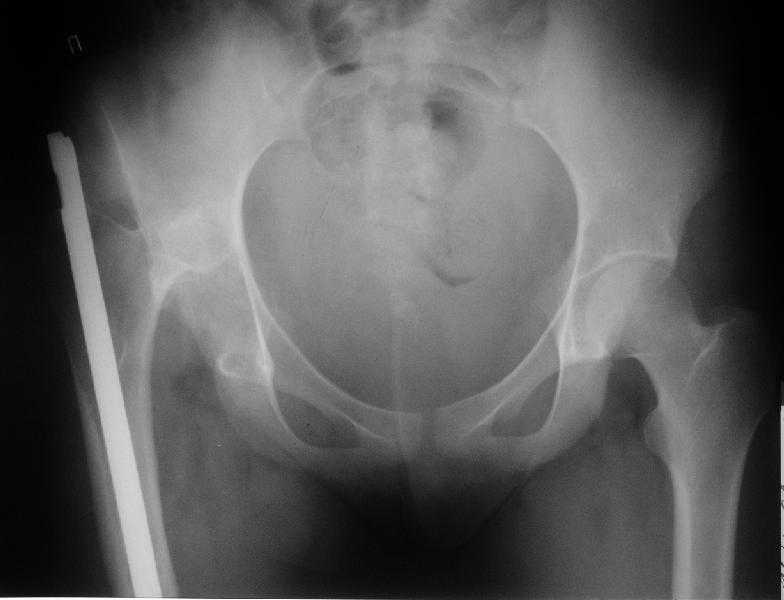

Поступила к нам в отделение. В отделении первым этапом был наложен аппарат внешней фиксации для низведения бедра. 30.09.08 интрамедуллярный стержень удален. Вторым этапом планируется эндопротезирование. В настоящее время у больной имеется контрактура коленного сустава, с амплитудой движений в пределах 30 градусов., и выраженный остеопороз вертлужной впадины и проксимального отдела бедра. Больныя пердвигается самостоятельно с опорой на здоровую ногу и костыли.

Какие проблемы при эндопротезиовании в этих условиях ожидать, и как с ними бороться? Еще и диафиз сросся не очень крепко, опасаемся, как бы не сломать. Очень выражен местный остеопороз, может быть, сделать все-таки цементный протез? Хотя 18 лет всего. Спасибо.

O kakom protezirovanii rech idet.Sdelaite srochno CT , esli net intraatricular fragments ya by poproboval soft tissue release and open reduction.THR vsega uspeete.

To be honest-nikakogo lichnogo opyta.Tolko vot chto mne meshaet : femoral head-normal, acetabulum-normal.Vhudshem sluchae budet arthrofibrosis and ankylosis, a potom let tak v30-40 THR.